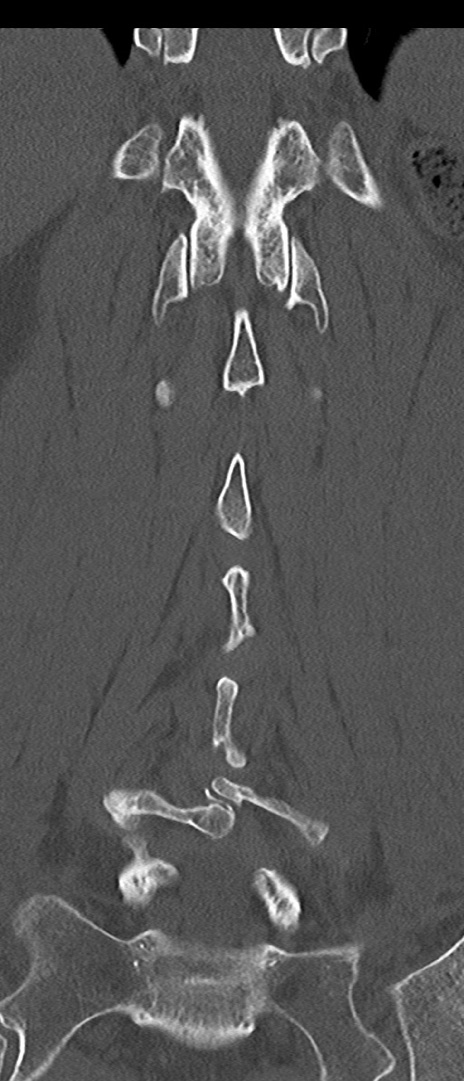

腰椎CT

矢状断像